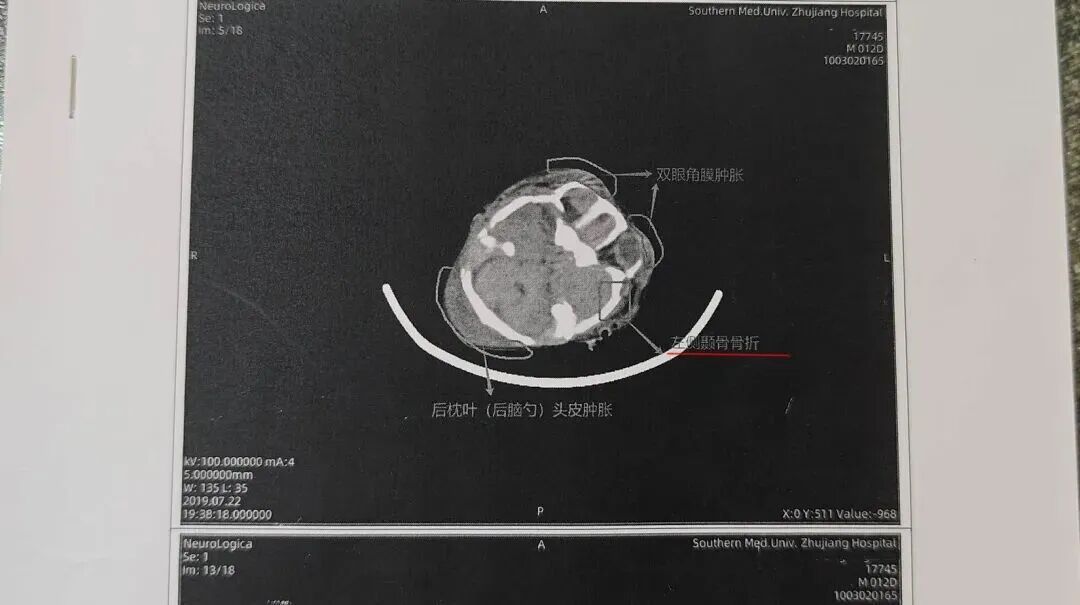

•2019年7月22日(出生第12天):CT显示双侧顶枕部软组织肿胀,医师判断为硬膜下及蛛网膜下腔积血、髓鞘发育未完全。

2025年3月至4月间,王莹夫妻俩将3张CT片发到专业医学影像交流群,还线下咨询了多位专家,得到的答案惊人一致:片子显示的症状,指向外伤。

社交平台上 多名医学专家的解答都指向“外伤、骨折”

2026年3月6日,《远程影像咨询意见书》出炉,明确诊断:孩子左侧颞骨、右侧颞骨、枕骨均骨折,矢状缝分离,伴随多处脑出血、头皮血肿。

北京一脉阳光影像中心在《远程影像咨询意见书》中指出患者有多处颅骨骨折